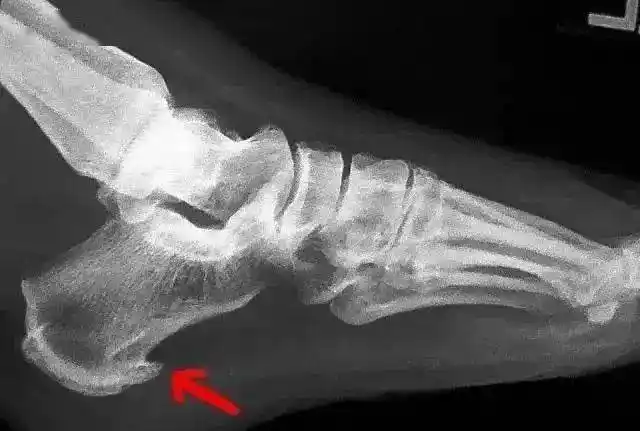

脚后跟疼是病吗如何治